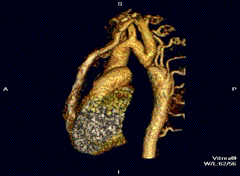

Koarktacja aorty przy użyciu różnych technik obrazowania. A. Zwężenie aorty w okolicy cieśni (strzałka). B. Obraz 3D z tomografii komputerowej z kontrastem ukazujący niewielkie zwężenie w okolicy metalowego stentu (strzałka), po poszerzeniu koarktacji – angioplastyka balonowa. C. Obraz w 3D z MRT z kontrastem ukazujący koarktację z bypassem (strzałka) omijającym koarktację. D. Obraz ukazujący duży tętniak rzekomy (grot strzałki) po uprzedniej plastyce z wszyciem łaty[13]

- ↑ Hopewell N, Hughes Marina L, Taylor Andrew M. The Role of Cardiovascular Magnetic Resonance in Pediatric Congenital Heart Disease, Journal of Cardiovascular Magnetic Resonance, 2011, 13, 51.(Koarktacja aorty. A. Ukośny rzut strzałkowy przedstawiający dyskretną, ciasną koarktację w miejscu cieśni aorty (strzałka). B. Angiogram TK 3D ze wzmocnieniem kontrastowym, pokazujący lekko zwężony stent z gołego metalu (strzałka), który częściowo pokrywa początek lewej tętnicy podobojczykowej. Grot strzałki przedstawia subtelny pseudo-tętniak na dystalnym końcu stentu. C. Angiogram 3D ze wzmocnieniem kontrastowym, obrazujący hipoplazję łuku aorty i koarktację z przeszczepem by-passu „omijającego” z tyłu (strzałka). D. angiogram MR 3D ze wzmocnieniem kontrastowym, pokazujący duży pseudo-tętniak (grot strzałki) po wcześniejszej operacji plastycznej angioplastyki. Prawdziwe światło jest pokazane z tyłu (strzałka)